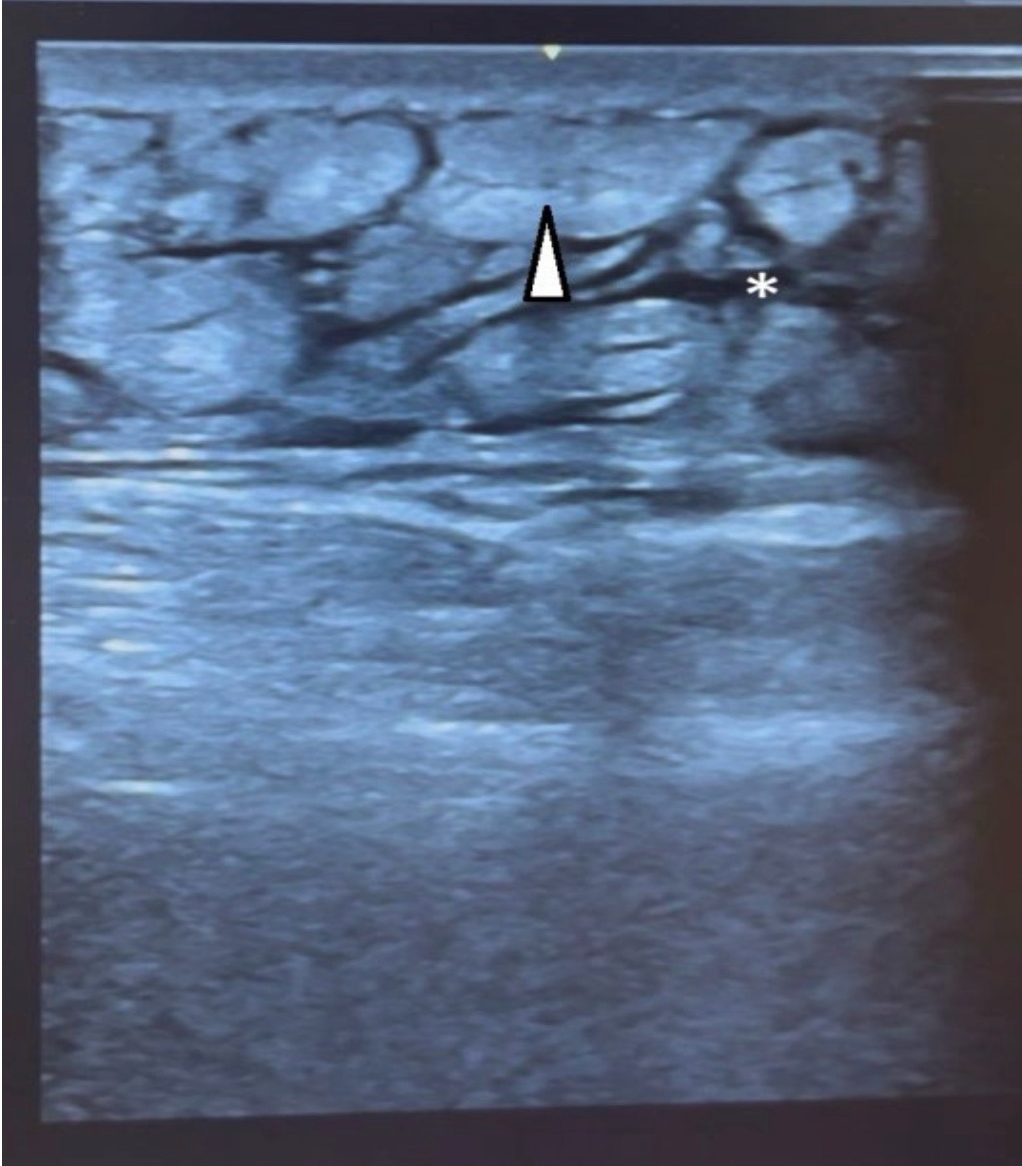

An 80-year-old patient presented to the emergency department with sudden onset of pain and swelling in his left leg that had occurred the day before. Ten days earlier, osteosynthesis of the pertrochanteric femoral fracture had been performed. The postoperative period was uneventful. He now denies trauma. He was afebrile and hemodynamically stable on admission. Clinical examination revealed swelling and tenderness of the left upper leg with warm, taut skin of normal color. Laboratory findings showed leukocytosis (12.7 × 10⁹/L), elevated CRP (124.7 mg/L), and elevated D-dimer (2.63 mg/L). Other findings were within reference values. Deep vein thrombosis was excluded by POCUS examination of the venous system of the lower limb, where the examined veins were properly compressible, without intraluminal echogenic masses. POCUS of the soft tissues of the left upper leg shows thickened and heterogeneous subcutaneous fat tissue with pronounced interstitial edema, a characteristic “cobblestone” appearance, without clearly delimited fluid collections and signs of abscess (Figure 3).

Figure 3. POCUS of the soft tissues of the left thigh showed thickened and heterogeneous subcutaneous fat with marked interstitial edema (asterix), a characteristic “cobblestone” appearance (white arrowhead), without clearly demarcated fluid collections and signs of abscess